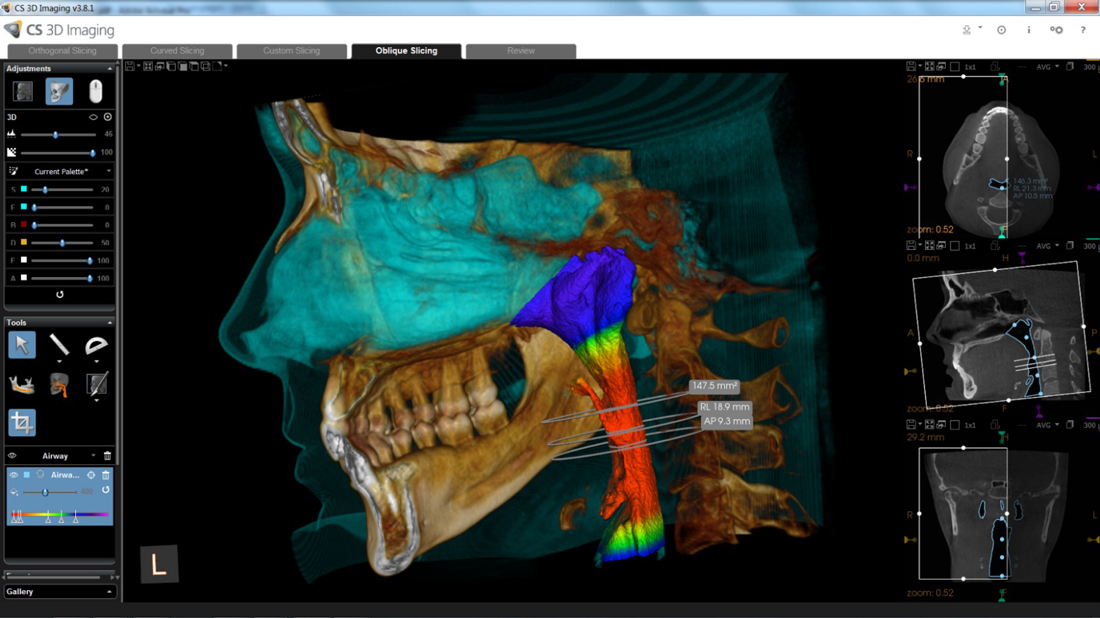

Exámen de Via Aérea Volumetría

Mediante el CBCT podemos analizar la vía aérea en toda su extensión tanto anteroposterior como lateral,

Lo que nos permite evaluar factores de riesgo para desarrollar OSA y predictibilidad de algunos tratamientos